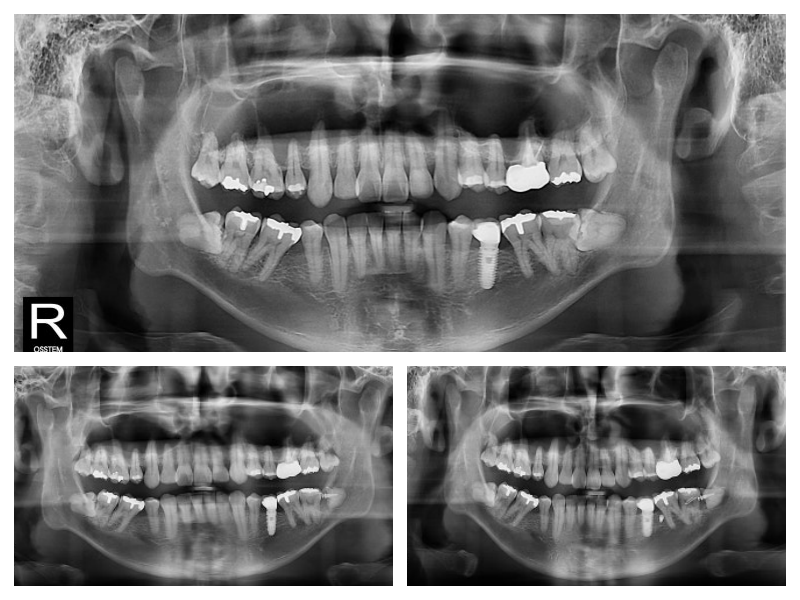

사랑니가 옆으로 누워있고 신경이라 가까워서 큰 병원 가서 뽑으래요~

사랑니뽑을 때 신경손상 나도 무섭다